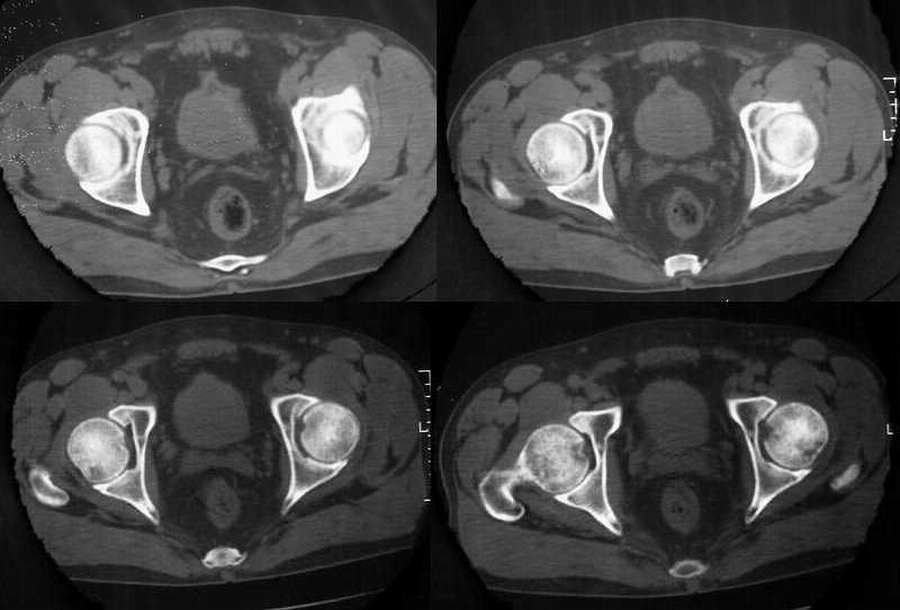

标题: CT2677:[原创]男54岁,左髋疼痛三月 [打印本页]

标题: CT2677:[原创]男54岁,左髋疼痛三月

盆腔静脉石;前列腺钙化;左股骨骨岛。

左侧股骨头无菌性坏死,盆腔静脉石;前列腺钙化;左股骨骨岛。

双侧都需要考虑股骨头无菌性坏死,其中左侧最为明显(囊变和碎裂)

本例就此图像无法明确有无股骨头缺血性坏死。

以股骨头缺血性坏死部位分为股骨头顶部和中心部持重区坏死与及其周边非持重区坏死。而本例左侧明显囊变在头颈结合部的下方。若两边都有问题,那么骨盆也显示密度不均,有问题吗?建议查mr或ect。

缺血性坏死的ct表现:(1)早期主要表现为正常股骨头骨小梁星状征变形,表现在从股骨头中央到皮质下有点状或小道样致密的骨增生,周围呈丛状或相互融合,关节下非持重部多以骨质疏松为主,股骨头完整,无明显碎裂;(2)病变区出现小范围坏死及小囊状影,继之股骨头坏死以持重区为明显,中央多呈楔形或周围新月状的骨密度增高坏死,囊变边缘硬化,正常骨结构可完全消失,坏死周围骨质梳松;(3)股骨头软骨头下骨折、塌陷,关节面不规则,关节间隙宽窄不一,股骨头可有轻中度变形,可有碎骨片落入关节腔;(4)晚期股骨头变扁、碎裂增加,外形不规整,呈“蕈伞”状畸形,其内见骨质增生硬化及透光区混合密度影,关节间隙变窄,髋关节退行性变。

双侧股骨头坏死可能性大,左侧为著,建议mri。

双侧股骨头无菌坏死,左侧为著